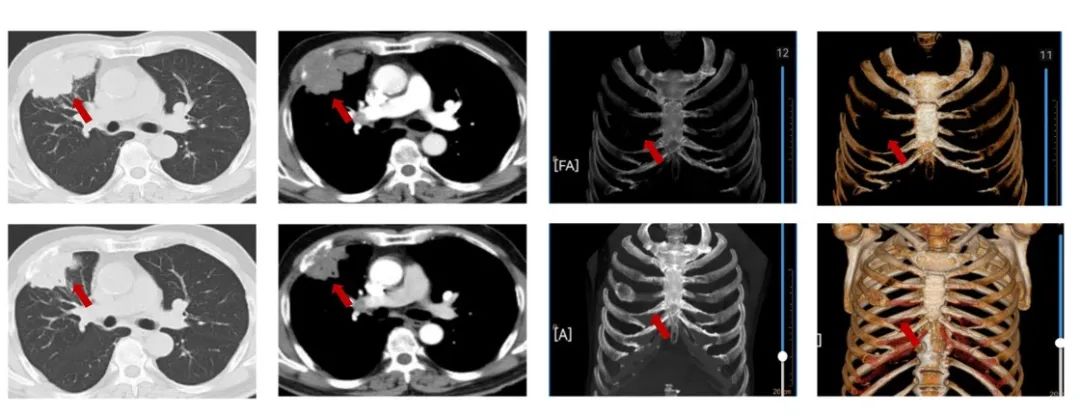

患者刘XX,男,65岁,2021年6月以“右胸痛2个月”为主诉入院,NRS7分,PS1分,吸烟30年,每天20支。外院胸部ct提示:右肺上叶团块影,PET/CT提示:右肺上叶前段可见不规则软组织肿块,范围约68mmx47mm,SUVmax=16.7,病变侵犯胸壁及右侧第4前肋;右肺上叶另见肿块及小结节,葡萄糖代谢增高。纵隔4R淋巴结代谢略增高,右肺上叶前段肺内转移;右肺门淋巴结代谢略增高,SUVmax=3.7,纵隔4R及右肺门淋巴结转移可能性大,未见胸膜增厚及胸腔积液,肝内钙化灶;气管镜取得病理,结合免疫组化为鳞状细胞癌,PD-L1(22C3)CPS=15。cT3N2M0 IIIB期,经MDT讨论后,为潜在可切除者先行免疫联合化疗,进行转化治疗,替雷利珠单抗+白蛋白紫杉醇/卡铂治疗3周期治疗,评效为缩小的SD。NRS 2分。

图1:由上至下分别展示基线(A.)及免疫化学治疗后改变(B.)。红色箭头指示病灶位置,由左至右分别为右肺肿物肺窗、右肺肿物纵隔窗、肋骨三维重建。

患者新辅助治疗无严重不良反应末梢神经炎I级,白细胞减少I级,心肺功能良好,3周期新辅助治疗后无手术禁忌证,患者于2021-09-02我院外科手术切除,术式:胸腔镜辅助下右肺上叶及部分中叶切除,下叶楔形切除,右侧第4肋骨部分切除,肺门纵隔淋巴结清除,胸腔粘连松解术。术后病理:肿物范围约5.2*2.6*2cm,侵透胸膜,侵及肋骨,肋骨长9.5cm,右肺上叶:见癌组织片巢状分布,浸润性生长,局部侵骨组织,见大量坏死。结合免疫组化及病史,鳞状细胞癌伴治疗后改变,侵骨组织。右肺下叶:纤维组织增生多量炎细胞浸润。淋巴结未见转移癌0/32:(D1)2组0/6、(D2)4组0/5、(D3)7组0/3、(D4)8组0/2(D5)10组0/7、(D6)11组0/3、(D7)12组0/2、(D8)13组0/2、(D9)14组0/2。pT3N0M0 IIB期,未达到MPR。术后行8周期替雷利珠单抗辅助治疗。目前患者生活质量良好,DFS已超过4年,仍在定期随访中。